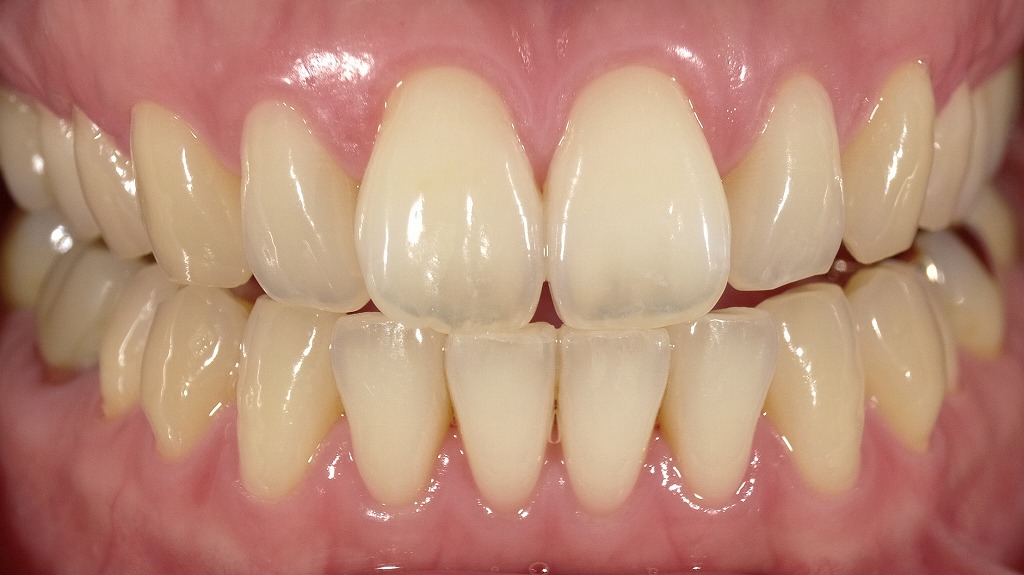

- 3.1.2.2. 2枚目:ホワイトニング後(A1シェードとの比較)

2枚目:ホワイトニング後(A1シェードとの比較)

2枚目では、シェードガイド「A1」が比較のために前歯の横に当てられており、

ホワイトニング後の歯がA1に非常に近い白さまでトーンアップしていることがわかります。

ポイント:

- 1枚目より明らかに白く、透明感も増している

- 自然な白さの中でも「明るさのレベル」が1段階以上アップ

- A1は「自然歯で達成できる最も明るい色のひとつ」